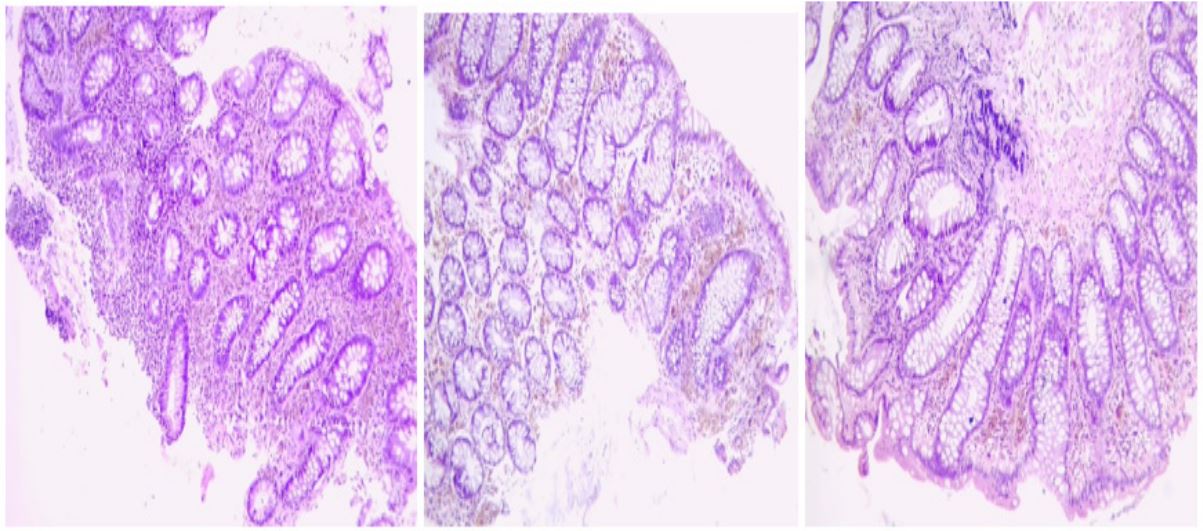

We present a 40 year old Nigerian female who presented with more than ten years’ history of chronic constipation. There was history of occasional anal pains and blood-stained stools over the past one year. She had associated recurrent abdominal discomfort which was usually relieved after passing hard stools. She had used various laxatives including herbs-based laxatives. She usually got some relief following the use of laxatives. Her physical examination findings were normal. Her basic blood investigations and abdomino-pelvic ultrasound scan were also normal. She was referred for colonoscopy on account of the chronic constipation and hematochezia with a working diagnosis of suspected Irritable Bowel Syndrome-Constipation (IBS-C) to rule out colorectal neoplasm. Colonoscopy showed brown-blackish discoloration of the mucosa of the caecum, ascending colon and part of the transverse colon (Figure 1). Mucosa of the descending colon, sigmoid and rectum appeared grossly normal. She also had internal hemorrhoids in the ano-rectal region on retroflexion of the colonoscope. Multiple biopsy specimen were taken from the different parts of the colon and sent for histology. Histology showed melanotic pigments within lamina propria macrophages and dense lymphoid follicles which confirmed the diagnosis of MC (Figure 2).

Figure 2: Histology microphotographs of our patient showing colonic type mucosa with melanotic pigments within lamina propria macrophages and dense lymphoid follicles.